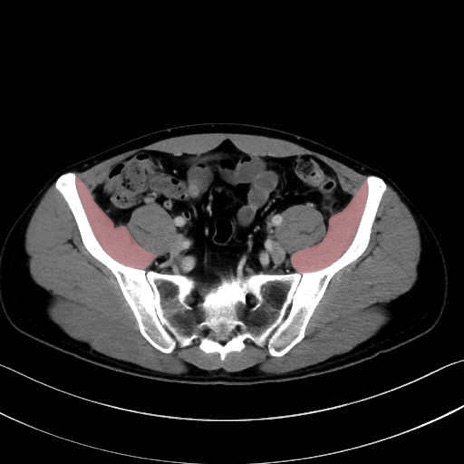

腸骨筋 (Iliacus)